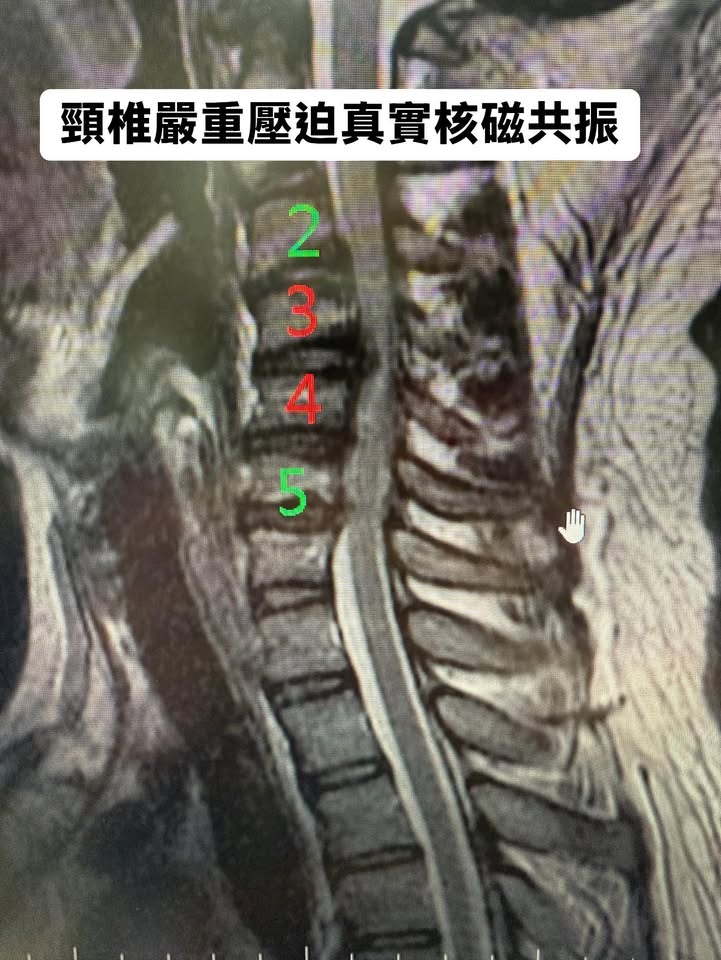

他是F-16戰鬥機的飛行員,年紀三十多歲,大好青春正在天空飛翔!駕駛過銀翼在天際中劃過無數弧線,承受過高達10倍重力的壓迫。然而,他的頸椎卻無法再撐住這樣的負擔。影像顯示,C3/C4/C5//C6神經被擠壓得像即將崩塌的橋樑,伴隨的症狀將他從戰鷹的高空拖回現實。